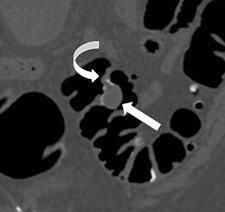

Along with his colleague Dr. Stefaan Gryspeerdt, Lefere has addressed CTC's potential pitfalls in a comprehensive paper published online January 4 in Insights into Imaging. Their top tips are to perform state-of-the-art CTC (preparation based on fecal tagging, along with colonic distension with CO2 plus injector, dual positioning, and smooth muscle relaxation), remember the general principles of interpretation, and take special care when examining the rectum and caecum.